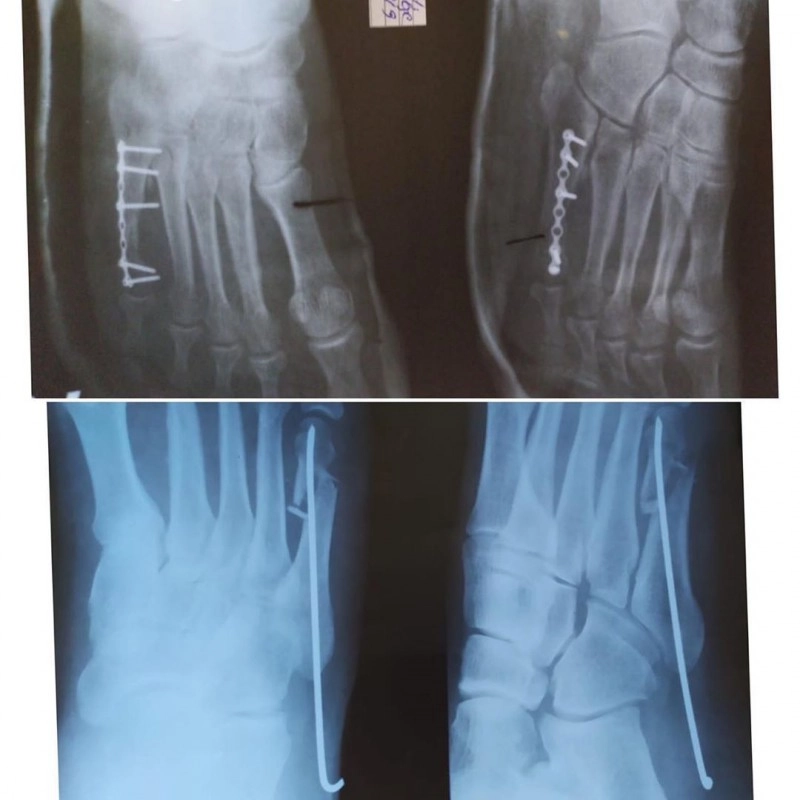

а также при переломах, в том числе для установки

металлических фиксирующих конструкций или их удаления.